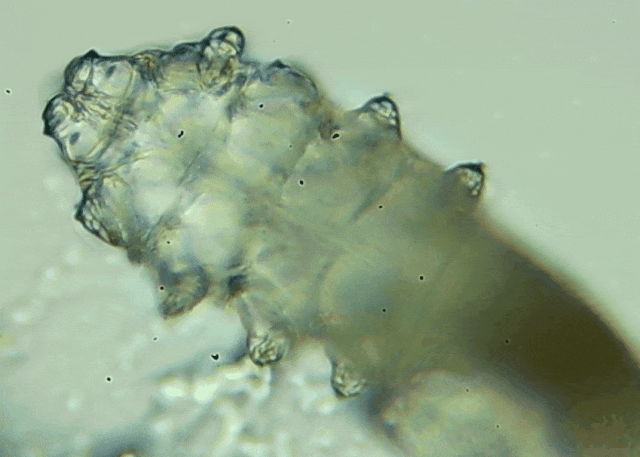

我只是眼睛癢,結(jié)果醫(yī)生說我睫毛里有80只蟲?這不是恐怖片,而是真實(shí)的病例:武漢一13歲男孩,右眼9根睫毛里檢出39只螨蟲,左眼9根里檢出47只。 而且這不是極端個案,廈門眼科中...

眼瞼位于眼球前面,分為上下眼瞼,而睫毛、一些腺體的開口和淚小點(diǎn)都在眼瞼邊緣,也就是瞼緣上。蠕形螨是一種寄生于毛孔、腺管和瞼緣上的螨蟲,因?yàn)轶w型微小,肉眼無法察覺。...[詳細(xì)]

瞼緣炎俗稱爛眼邊,它是瞼緣表面睫毛毛囊及其附近腺體的亞急性或慢性炎癥。是一種非常普通的眼病,短期內(nèi)不易徹底治愈。 為什么會得瞼緣炎呢?眼科中心專家醫(yī)生為我們解答,什...